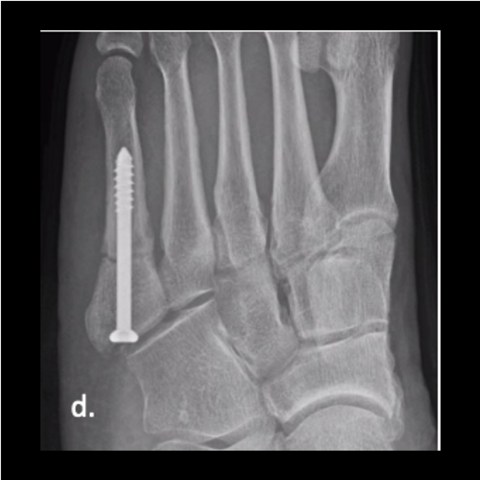

Figure 4e

Figure 4e. The 24-year-old soldier jumped off the back of a truck, refracturing his metatarsal. Here is the foot a year post-surgery after jumping off the truck.